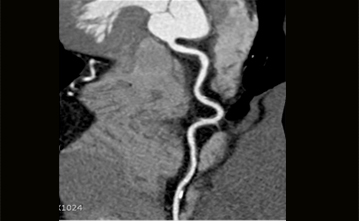

경피적 심혈관조영술과 같이 침습적이며 입원을 하여 시행하는 검사외에 외래에서 검사할 수 있는 CT 혈관 촬영술이 있습니다. 이는 6시간 정도의 금식이 필요하며, 다른 장기의 CT촬영과 방법이 같습니다. 조영제를 사용해서 혈관을 보는 검사방법이여서, 신장기능과 같은 기본 혈액검사의 결과를 확인 후 조영제를 정맥주사를 통해 주입하여서 그림과 같은 관상동맥의 구조와 협착정도를 눈으로 확인할 수 있게 됩니다. 입원의 절차도 필요없고, 동맥천자와 같은 침습적인 방법도 시행하지 않는다는 간편성은 있지만, 병변의 진단만 가능한 검사이며 심각한 협착이 발견된다면, 침습적 혈관조영술이 추가 필요하게 될 수도 있습니다.